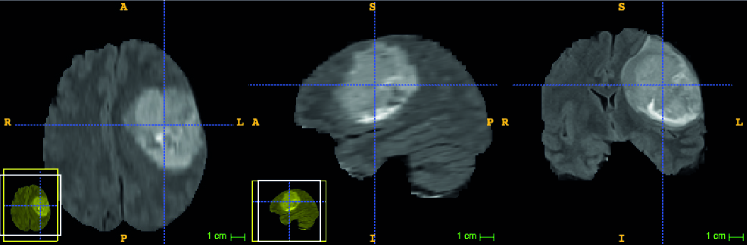

More specifically, 3D stacks such as those depicted by Fig. 1 are common in the biomedical field and are particularly challenging, in part because it is difficult both to develop effective interfaces to visualize the huge image data and for users to quickly figure out what they are looking at. In this paper, we will therefore focus on image volumes but the techniques we will discuss are nevertheless also applicable to regular 2D images by treating them as stacks of height one.

Similarly, batch-mode selection [28, 11, 29, 5] has become a standard way to increase the efficiency by asking the expert to annotate more than one sample at a time [23, 2]. But again, this has been mostly investigated in terms of semantic queries without due consideration to the fact that, in images, it is much easier for annotators to quickly label many samples in a localized image patch than having to annotate random image locations. In 3D image volumes [16, 12, 8], it is even more important to provide the annotator with a patch in a well-defined plane, such as the one shown in Fig. 2, rather than having him move randomly in a complicated 3D volume, which is extremely cumbersome using current 3D image display tools such as the popular FIJI platform depicted by Fig. 1. The technique of [33] is an exception in that it asks users to label objects of interest in a plane of maximum uncertainty. Our approach is similar, but it also incorporates geometric constraints in query selection and as we show in the result section, it outperforms the earlier method.

We then automatically select the best plane through the 3D image volume in which to label additional samples, as depicted in Fig. 2. The expert can then effortlessly label the supervoxels from a circle in the selected plane by defining a line separating target from non-target regions. This removes the need to examine the relevant image data from multiple perspectives, as depicted in Fig. 1, and simplifies the labeling task.